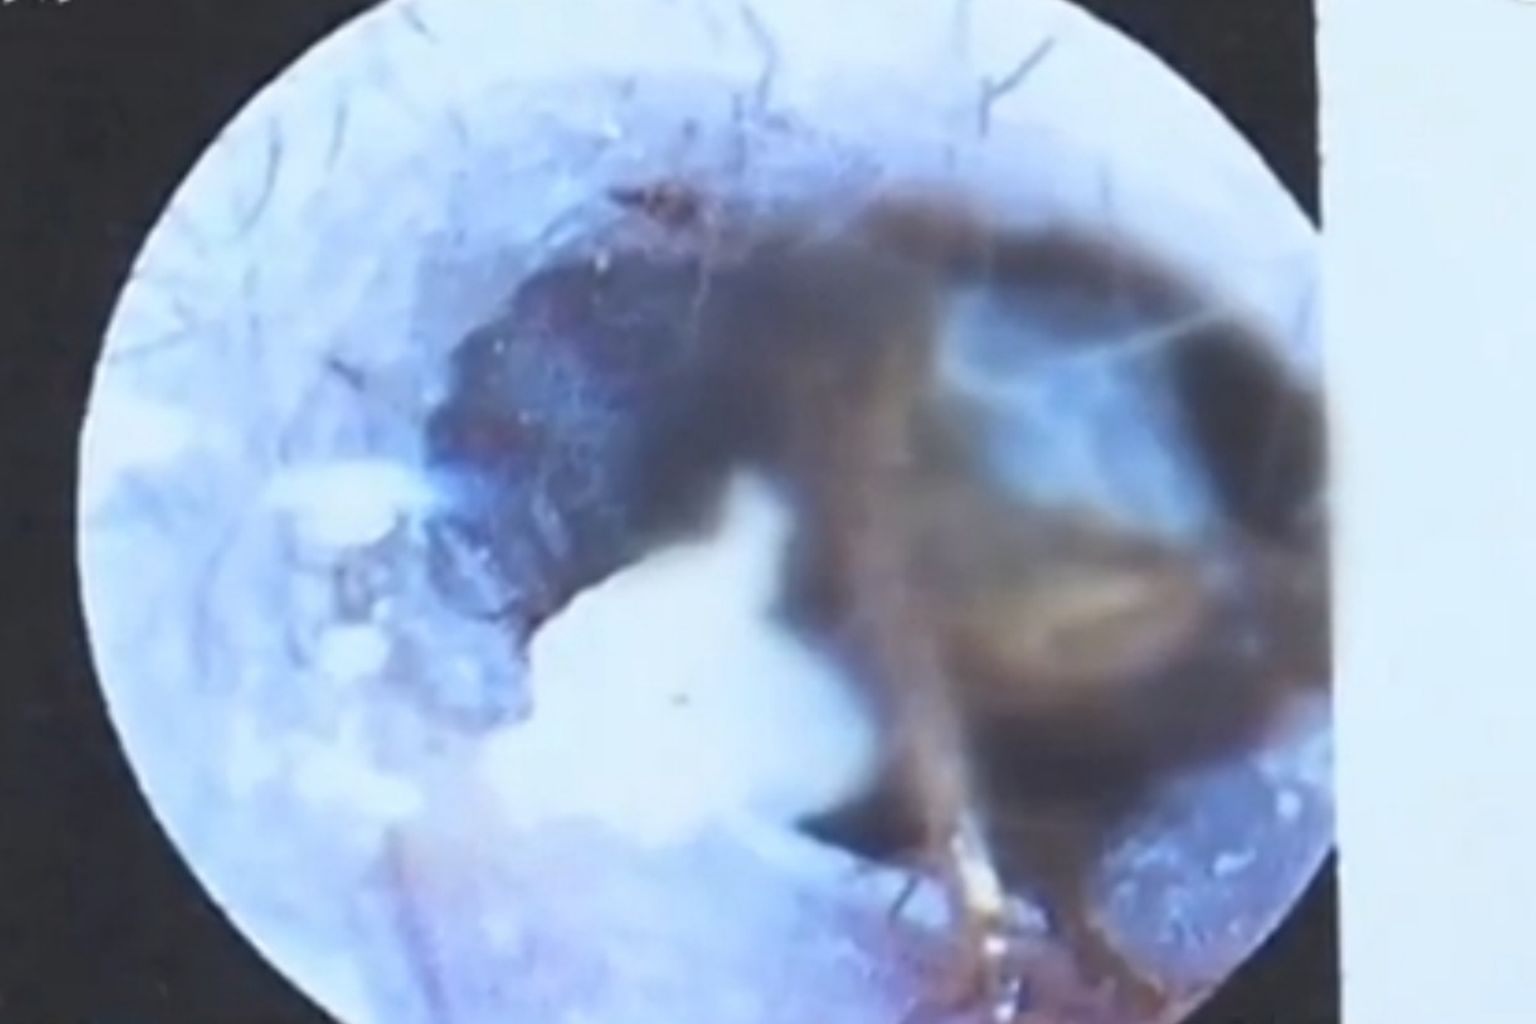

Cockroach crawls into Chinese woman's eardrum and chews a small hole

The woman said she experienced a sudden pain in her right ear and the feeling that an insect was scuttling about inside.

Two days later, doctors told her that the cockroach had chewed a small hole in her eardrum.